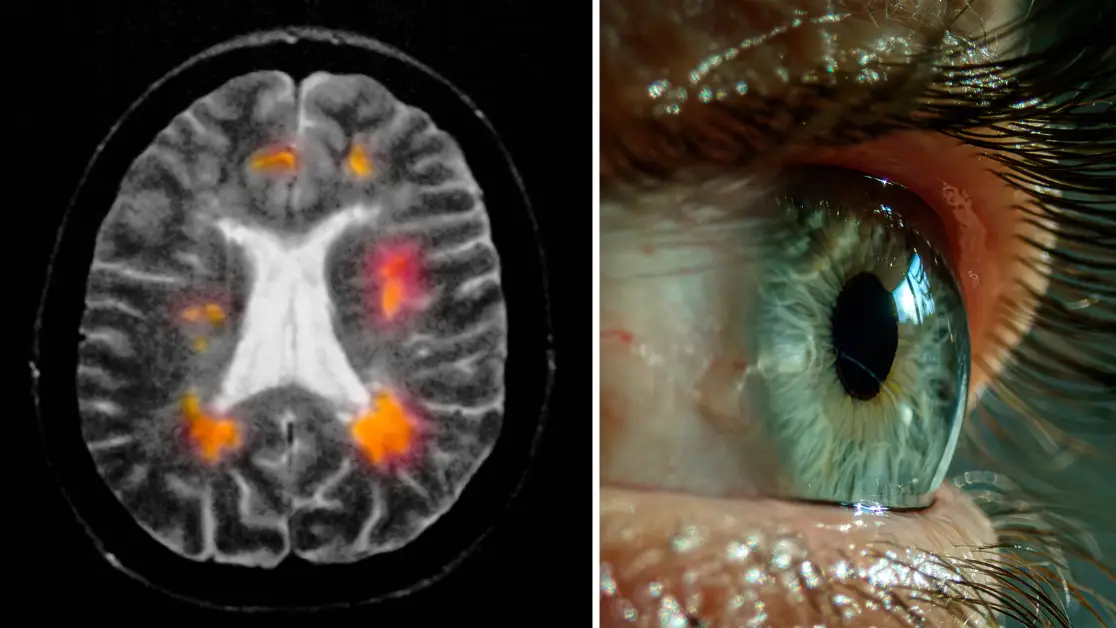

a year agoEarly sign of MS to look out for that could appear in your eyesNo two people with the unpredictable condition experience the same symptoms News